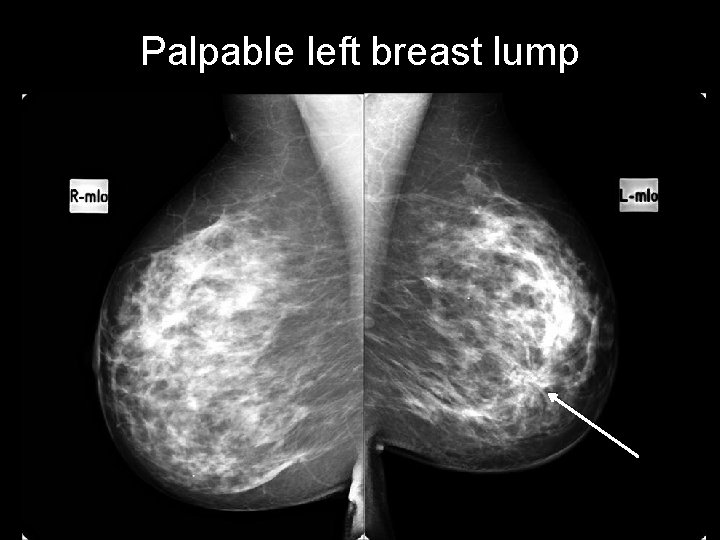

Palpable left breast lump

Palpable left breast lump architectural distortion area of architectural distortion with pleomorphic calcifications microcalcifications

Palpable left breast lump a region of architectural distortion and pleomorphic calcification BREAST CARCINOMA http: //radiopaedia. org/cases/breast-carcinoma